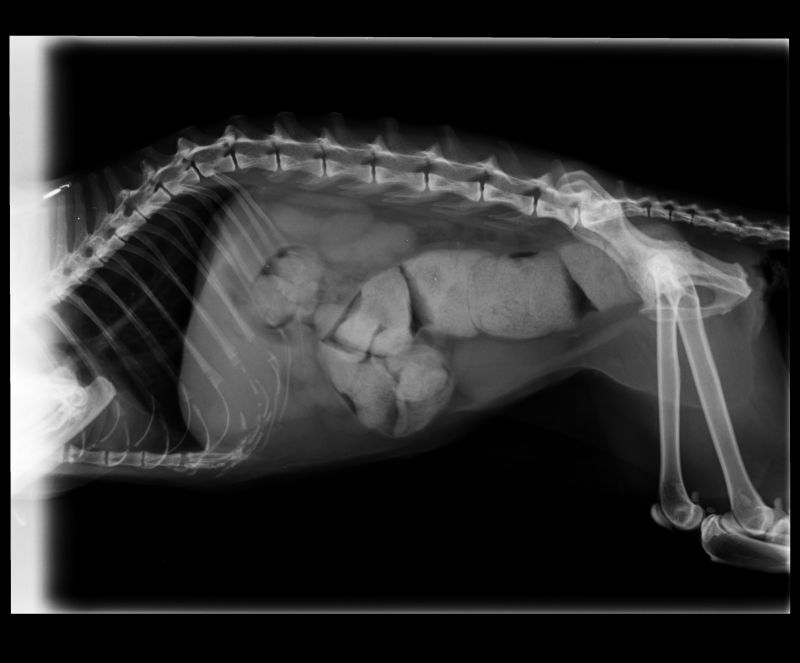

Abnormal Pathology on your pet

Shown on x-ray images which we have taken over the years.

Some interesting patient cases